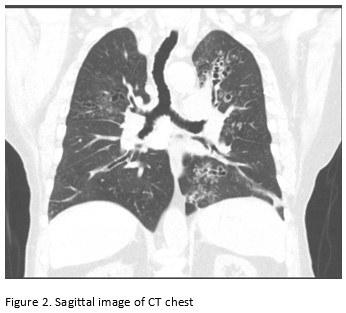

A 65-year-old male with poor healthcare follow-up presents to the pulmonary clinic with “years of breathing problems”. He reports shortness of breath and cough productive of grayish-brown sputum. He denies fevers, chills, weight loss, hemoptysis and night sweats. He denies recent travel history. His physical exam is significant for scattered wheezes bilaterally. Labs are significant for peripheral eosinophilia of cells/microL (21.7% eosinophils) and elevated total Ig E level of 2385 IU/ml. Representative images of his CT chest are shown below.

Images